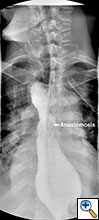

A 49 year old male presented to our institution with significant dysphagia and a 40 lb. weight loss secondary to a distal esophageal stricture. The patient had ingested lye 4 years previously and required partial gastrectomy, gastrojejunostomy, and partial colectomy at an outside institution at that time. His symptoms of dysphagia had progressively worsened despite repeated dilations and placement of an esophageal stent (Figure 1). Surgical reconstruction was therefore felt to be indicated. Preoperative computerized tomography angiogram did not clearly display the blood supply to the stomach, but did show that the colonic vasculature was adequate for use as a conduit if needed.

Figure 4. Postoperative barium swallow demonstrating free flow through the anastomosis with no residual stricture.

The patient had an uncomplicated course. His nasogastric tube was removed on postoperative day five. A water-soluble esophageal swallow study on postoperative day six demonstrated normal flow of contrast through the anastomosis and stomach into the jejunum, with no evidence of leak or obstruction (Figure 4). The patient was discharged to home on regular diet on postoperative day eleven. Pathologic analysis of the specimen revealed multiple strictures within the esophagus, to a diameter as narrow as 5 mm, and no evidence of malignancy. The patient had complete resolution of his dysphagia on 9 month follow-up and was returning to his baseline weight.